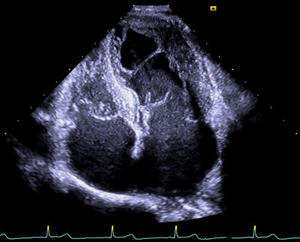

True Volume TEE Imaging

僧帽弁・大動脈弁を含む広範囲の3D画像や血流情報を加えた3Dカラードプラを心電図同期なく,リアルタイムに描出します。画像取得時の呼吸コントロールが必要なく,術後の弁周囲逆流の評価なども瞬時におこなえ,より安全で確実な施術に貢献します。